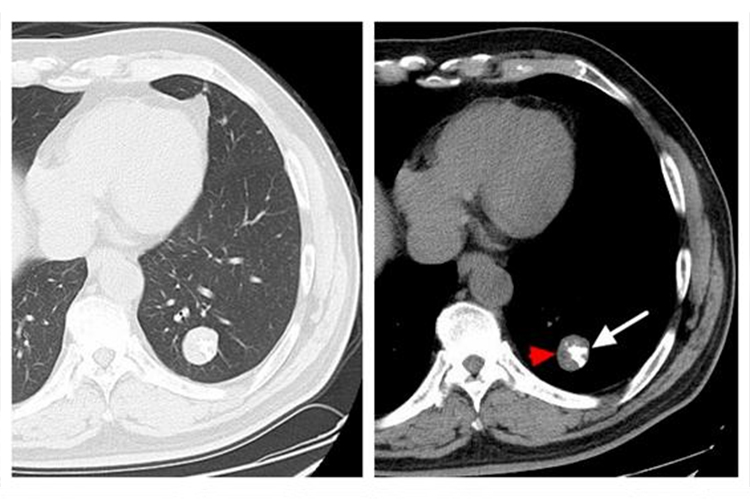

1、肿瘤位置特殊:肺部纵隔内结构复杂,包含着许多重要的器官和血管,如心脏、大血管、气管、食管等,如果纵隔肿瘤的位置紧邻重要结构,手术难度会极大增加。在手术过程中,稍有不慎就可能损伤到这些关键部位,导致严重的并发症甚至危及生命,若肿瘤与大血管紧密粘连,分离肿瘤时可能会引起大出血,难以控制。